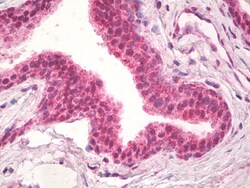

Invitrogen™ NPR3 Polyclonal Antibody

Additional Information: The immunizing peptide represents the cytoplasmic part of the protein. This antibody is tested in Peptide ELISA: antibody detection limit dilution 1:16,000.

| Immunohistochemistry (Paraffin), Western Blot | |